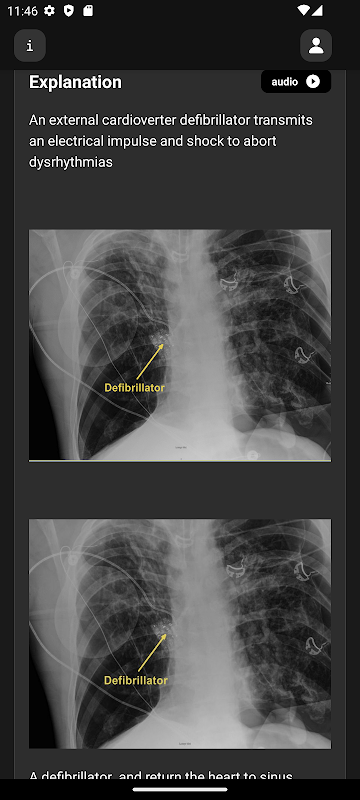

Imej, video dan animasi radiologi berkualiti tinggi

Penerangan terperinci untuk setiap soalan